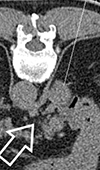

Adrenal Lesion Core Biopsy: A New Approach and an Incidental Benefit

A 79-year-old male with a history of renal cell carcinoma was referred for CT guided core biopsy of a right sided 3 cm adrenal lesion. A number of vul... Read more